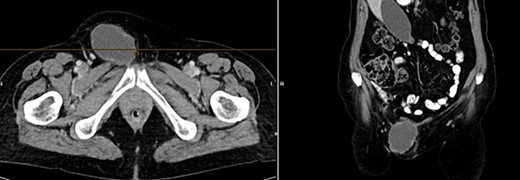

A month later, the patient presented again as the mass in the left groin area had increased in size. A CT (Fig 4) and another excision biopsy were performed. Histological examination revealed parts of a pleomorphic, most likely mesenchymally differentiated neoplasm. It was determined that the presence of a metastasis of the known prostate carcinoma could be ruled out. A myxofibrosarcoma was considered as a differential diagnosis, although the proliferation rate was rather low for this. Therefore, a reference pathology review was initiated.

CT of the abdomen from 26 July 2023: size-progressive metastasis in the left groin with infiltration of the adductor muscles; no dynamics in the primarily osteoplastic diffuse osseous metastasis.